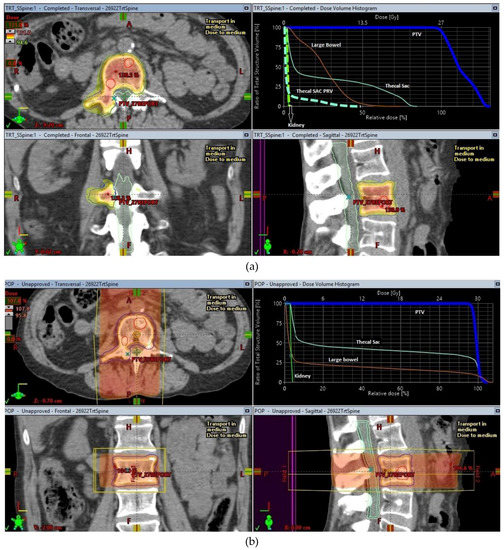

The origins of SBRT are linked to intracranial stereotactic radiosurgery, a concept pioneered and carried forward to full clinical execution by Prof. Lars Leksell [3] with the creation of specialized radiosurgery machines like the Gamma knife® to treat brain tumours. Early work by Lax and Blomgren at the Karolinska Hospital in Stockholm helped to establish the feasibility of high-dose radiotherapy treatments in the extracranial setting [4,5], using stereotactic body frames for achieving the required degree of accuracy that these treatments required. As radiosurgery started to become an established method of treating intracranial lesions, it led to more research into making radiosurgery less invasive. This in turn helped to drive continuing improvements in the delivery of this treatment using more common radiotherapy delivery platforms like linear accelerators. An illustration of the conformal dose distribution achievable with SBRT in comparison to conventional RT for a spinal metastasis is shown in Figure 1.

SBRT has a high rate of achieving local control in oligometastatic disease in sites like the spine where surgical intervention can be a high-risk undertaking. The use of SBRT for treatment of spinal oligometastatic disease was the second most frequent indication (after primary lung cancer) for use of SBRT in the SEER database. The concern about using higher doses of radiotherapy for control of spine metastases largely centered on the relatively low radiation tolerance of the spinal cord. This is especially a problem when the segment of spine has been previously treated with radiotherapy either for the same metastases or to an adjacent tumour, e.g., in the case of paravertebral lung tumours. With the use of magnetic resonance imaging (MRI) scans of the spine, specifically done for the radiotherapy planning process, the spinal cord and cauda equina are better visualized. This imaging was combined (co-registered) with the treatment planning CT imaging to achieve delineation of the spinal cord accurately on the radiotherapy treatment planning software in preparation for SBRT planning. International consensus guidelines on delineation of the target volumes have been published [62] and have led to standardization of the volumes treated with Spine SBRT in most centers. In addition to these improvements, the use of rigorous image guidance which has become the hallmark of SBRT treatments, to accurately correct millimeter changes in spine or patient position during delivery of the treatment, allowed SBRT to minimize the risk of radiation myelopathy by controlling the dose delivered to the spinal cord and other organs at risk (as shown in Figure 1a).

Figure 1. SBRT and conventional treatment plans for a lumbar spine oligometastases. (a) SBRT plan for lumbar spine oligometastasis, (b) Conventional radiotherapy plan for lumbar spine oligometastasis.